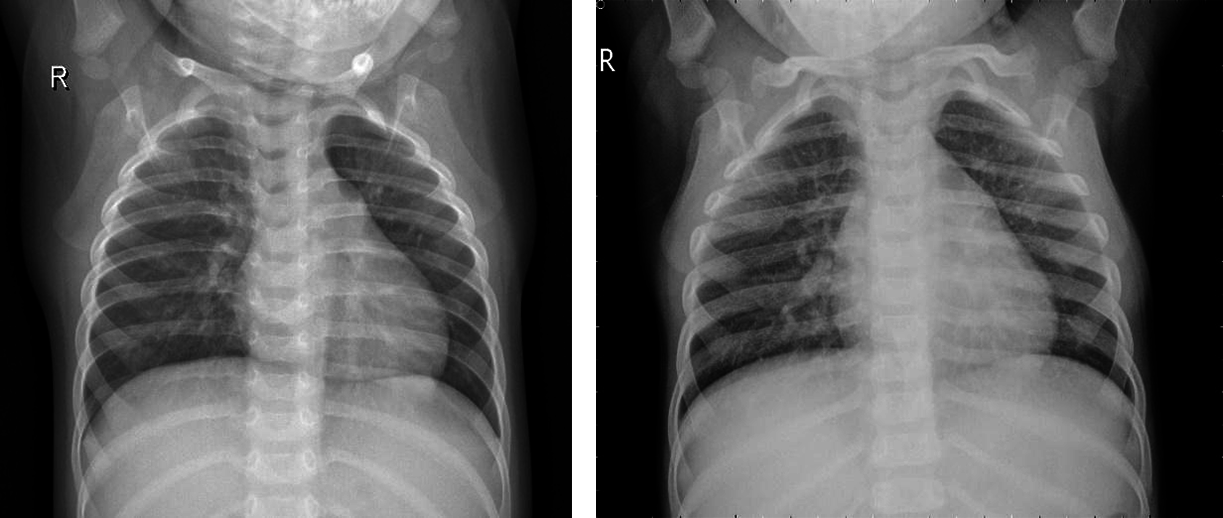

The dataset images, which are divided into two parts. Those are Covid positive and normal CXR images. The images are then converted into (224,224) forms and normalized. At that point, the pictures are rearranged and split into preparing and testing information. Thus, the training part has 60 images and 2 classes. The same testing part has 60 images and 2 classes. There are many possibilities that the same patients’ CXR images are kept in both the training and testing parts. It can be overlapping, but it’s kind of promising that training of the model, which has been examined by testing and validation checking, defines the ability of the trained model. Covid-19 positive and negative patients’ chest X-Ray images below in Figs. 5 and 6.

Figure 5: Covid-19 positive patient CXR pictures

Figure 6: Covid-19 negative patient CXR pictures

Here are 4 images from the dataset which have been taken from the Kaggle dataset. Covid and Normal. The first dataset was distributed in 2018, and from that point forward, around 100 exploration articles have 121 been distributed so far, including its example. The benchmark paper by Kermany et al. reports 122 claims a grouping exactness of 92.8 percent while utilizing the Inception V3 architecture (pre-prepared for the 123 ImageNet datasets) to recognize Normal and COVID tests. When it came to recognizing normal, bacterial, and viral pneumonia, they achieved a 90.9 percent accuracy rate. Notwithstanding, 125 ongoing examinations have revealed better order results (for paired groupings) on these 126 datasets. For instance, in 2020, Chouhan et al. detailed an examination portraying a Transfer Learning127 based methodology for Covid identification, which brought about a 96.39 percent grouping exactness 128. Nahid et al. suggested a two-channel CNN-based pneumonia location technique that generated a 132-characterization exactness of 97.92 percent [23]. They utilized five diverse pre-prepared CNN structures, including extraction and a 129-troupe procedure for the last grouping. Mittal et al. [13] used Dynamic Capsule Routing 130 to achieve a maximum categorization accuracy of 95.90 percent using the second dataset [17]. The creators utilized numerous pictures preparing strategies 133 to deal with the examples prior to playing out the grouping utilizing the profound learning model. Covid-19, a CNN-based design with 21 layers, including standard 135 and the depth of the astute detachable convolution operations, was introduced by R. 134 Siddiqi. Different parallel arrangements of 136 were used in that review to recognize pneumonia, and Covid-19 accomplished a 94.80 percent 137 arrangement exactness on the testing tests. For pneumonia identification, Hu et al. presented MD-Conv, a multi-portion, profound, and comprehensive 138 convolution plot. On the popular Chest X-beam 14 dataset, they tested their 139 methods and got a 98.30 percent Area Under the Curve (AUC) 140 score. 141 A little research, such as the 142 suggested approach, used chest X-beam images to perform three-class characterization, including the initial dataset. Mahmud et al. 143, for example, presented CovXNet (a multi-enlargement CNN) for normal and COVID-19 identification and 144 Covid-19 arrangements in 2020. They tried various layouts using subsets of 145 of the two chest radiograph datasets and a variety of deep learning models. In any case, they 146 accomplished pinnacle results by utilizing CovXNet with adaptable multi-open element 147 advancement. Using CNN and Transfer Learning, Jain et al. achieved three-class characterizations to recognize Covid and its 148 types. To fulfill their objective, they looked at several avenues using 149 six different CNN-based models, four of which were pre-prepared 150 models, similar to the former inquiry [23].